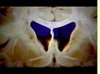

Which numbers are the: caudate nucleus putamen internal capsule lateral ventricle

Which numbers are the: caudate nucleus: **8** putamen: **12** internal capsule: **9** lateral ventricle: **19**

Label 3, 4 & 9 [3]

3: **Head of caudate nucleus** 4: **Putamen** 9: **Internal capsule**